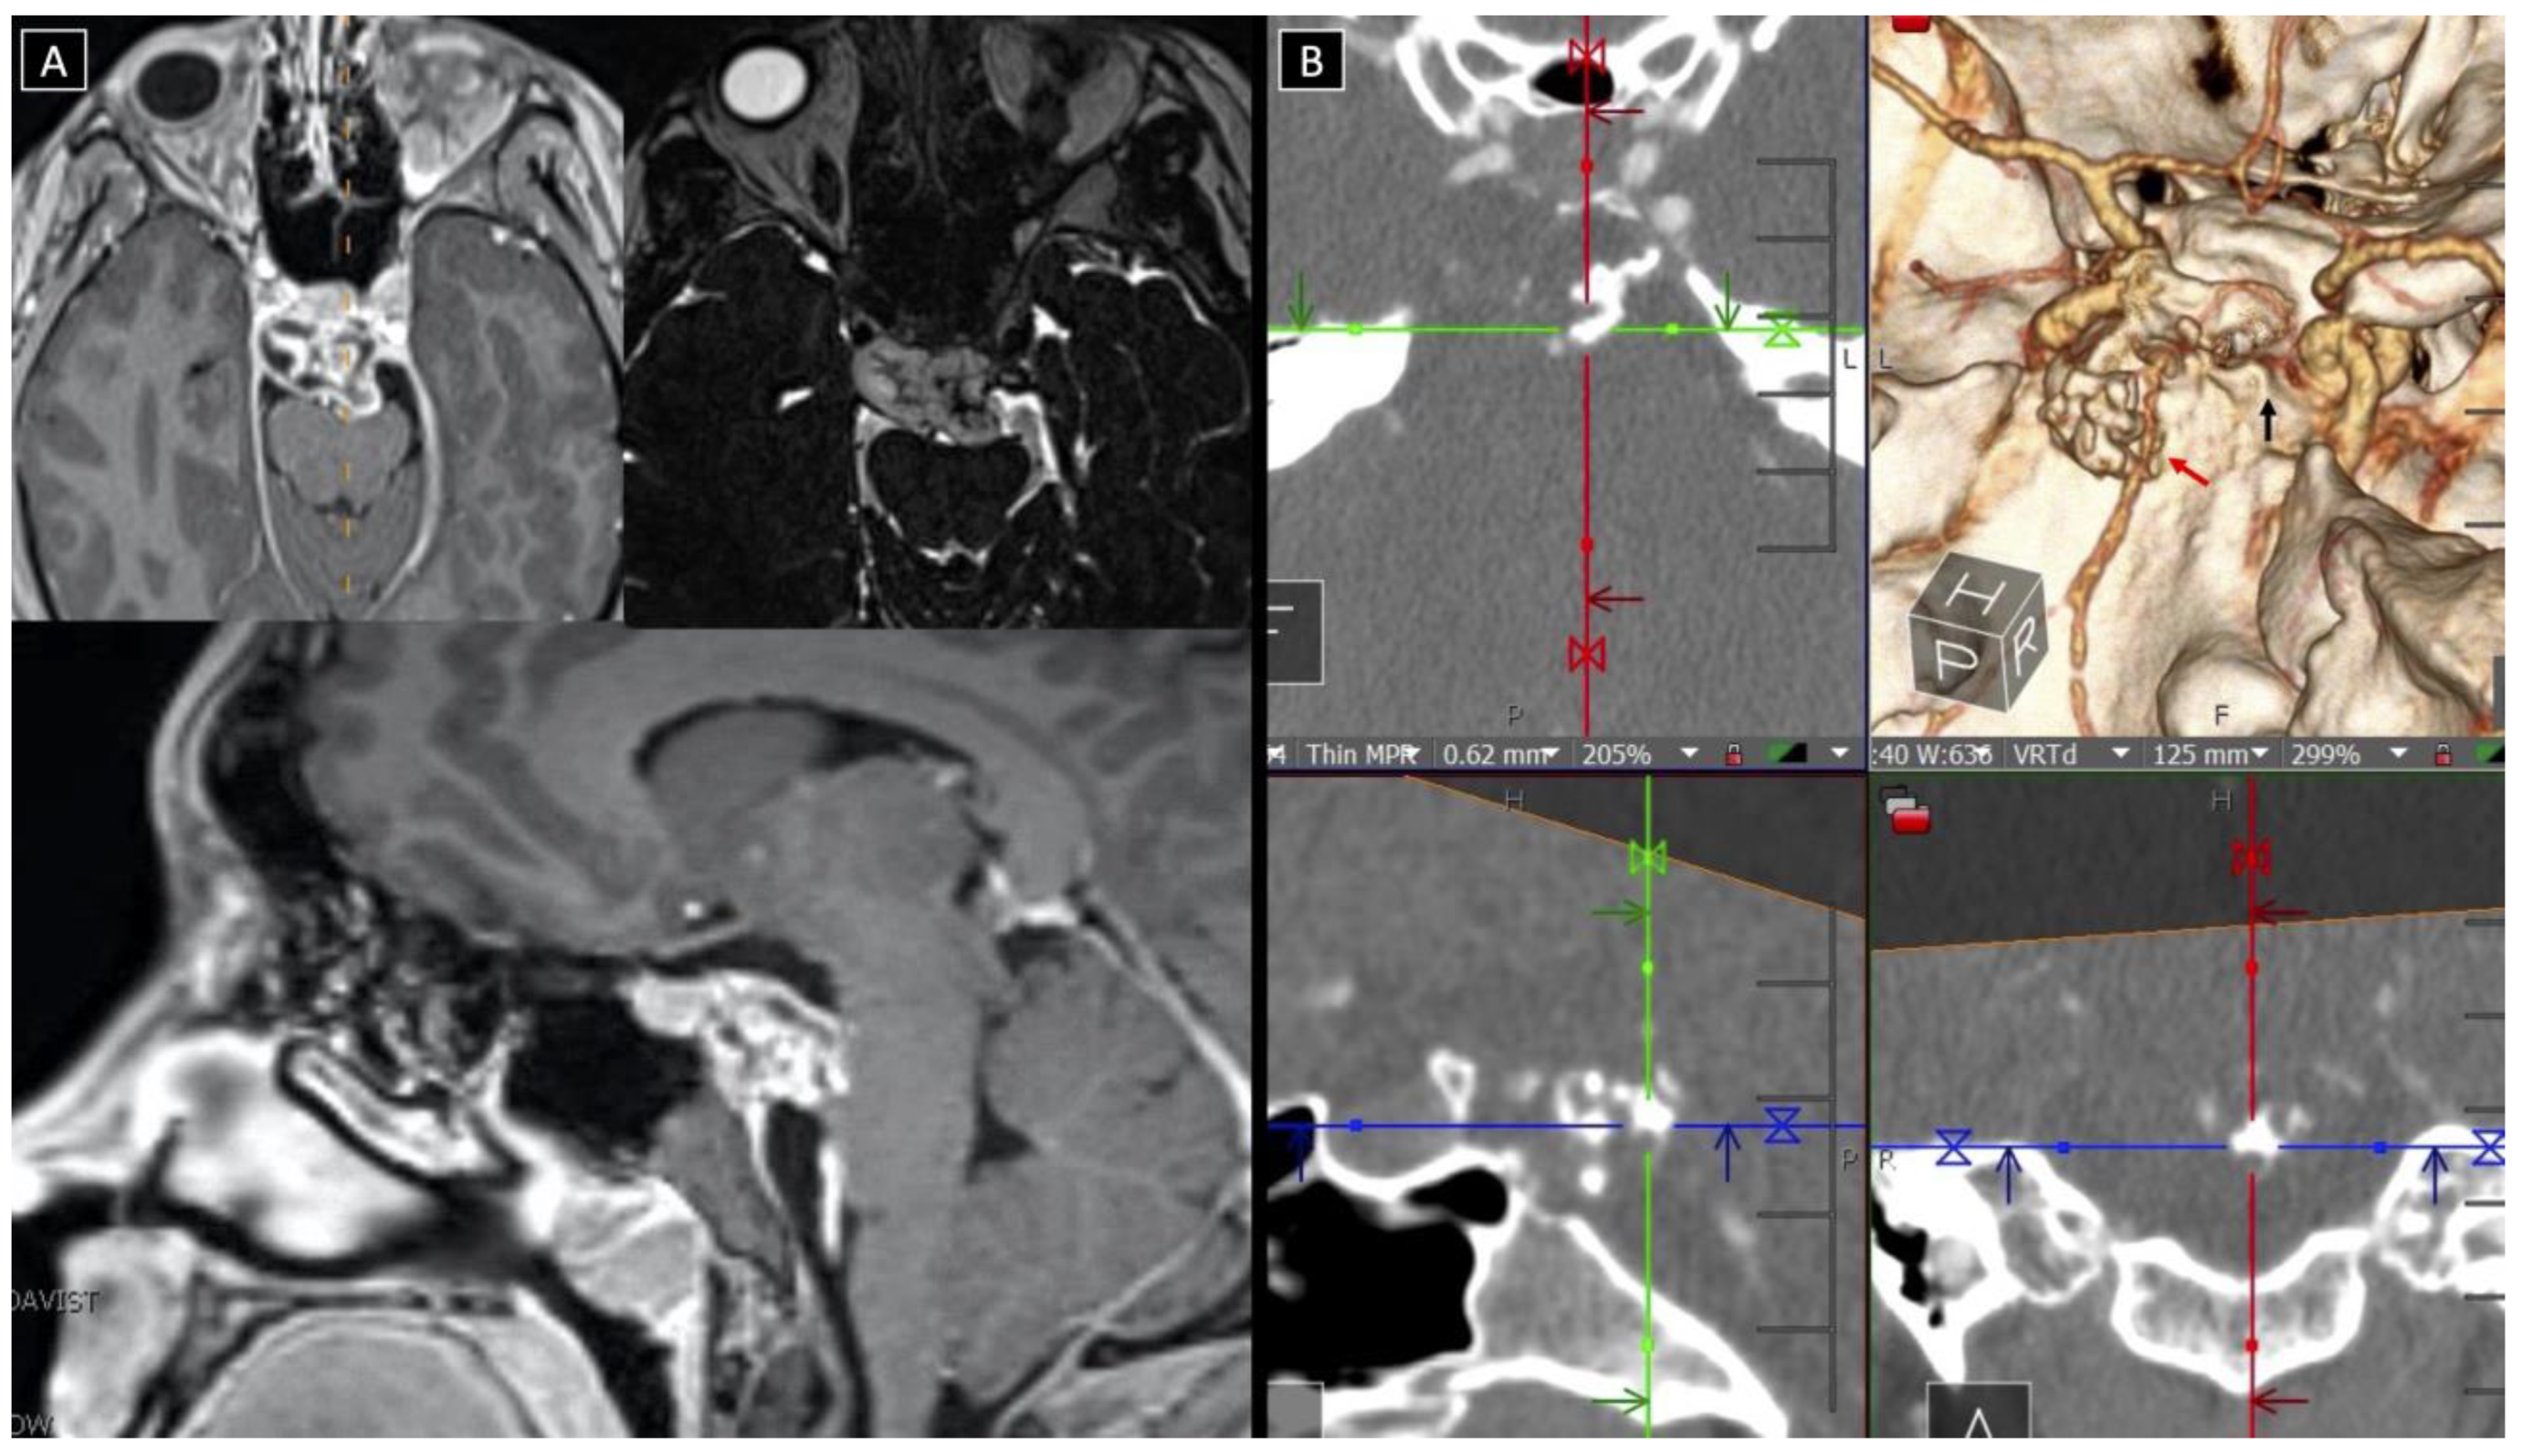

3.5.1. Case 1

3.5.2. Case 2